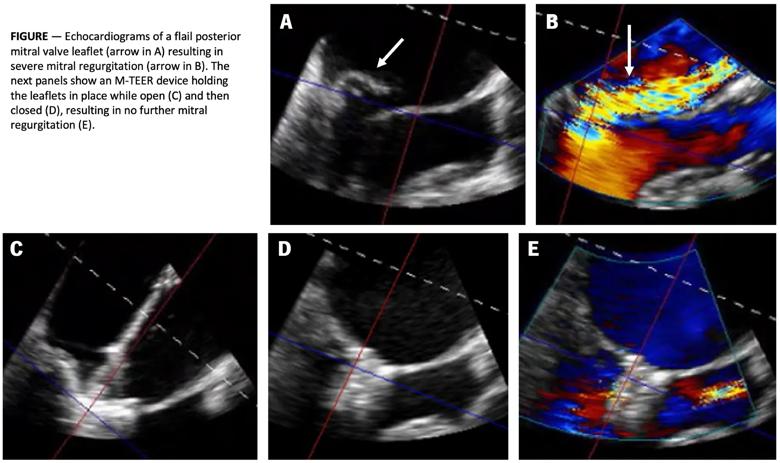

In the United States, the most common cause of primary MR is a flail mitral valve leaflet due to fibroelastic deficiency (Figure). For patients with this presentation, surgical valve repair (or replacement, if necessary) remains the gold-standard treatment.

five echocardiogram images of the heart with a figure caption